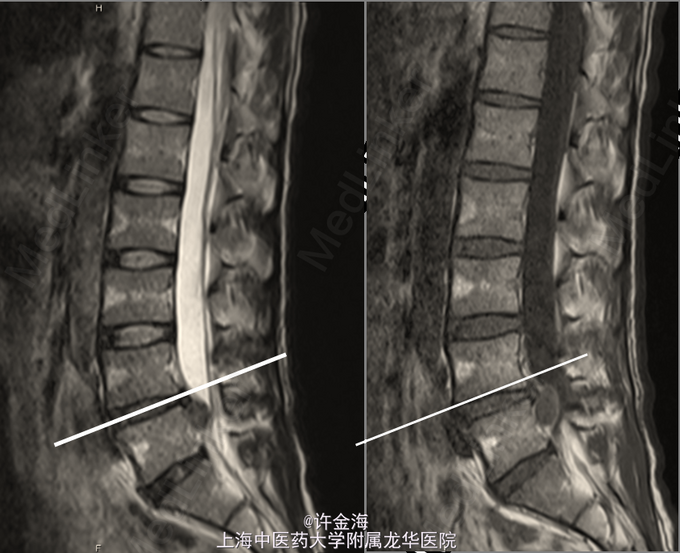

单阶段巨大椎间盘突出,融合OR非融合?

主诉:男,44岁。腰痛伴左下肢麻木、放射痛 一周

腰椎间盘突出症 术前:VAS腰6分,VAS腿8分,JOA12分 行全椎板切除减压,椎间盘摘除,cage融合,植骨内固定